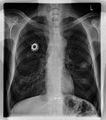

Röntgenaufnahme des Thorax (Projektionsbild)